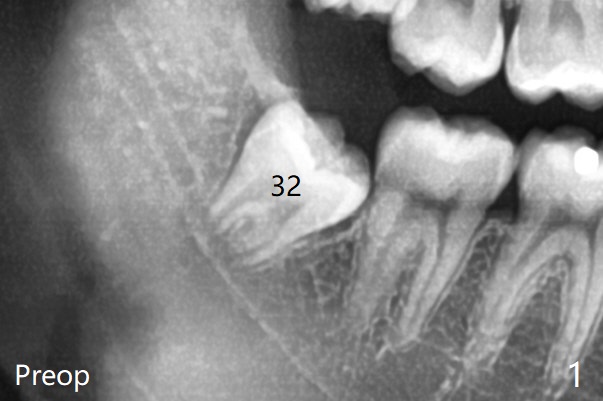

To prevent dry socket, collagen plug is placed at #17 and 32 post extraction (Fig.2).